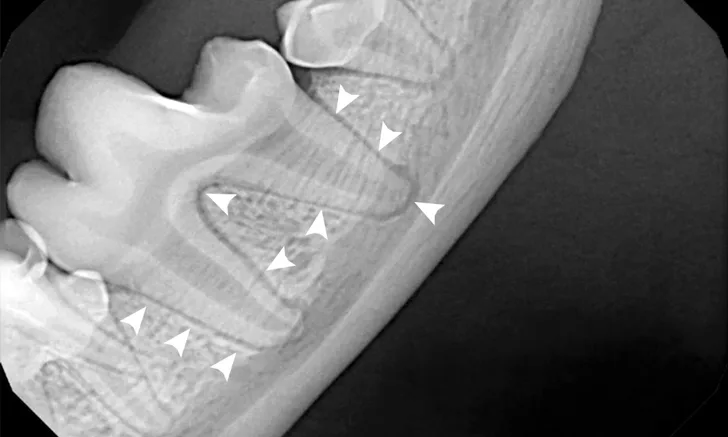

Dental x-ray of mandibular first molar with arrowheads pointing to normal periodontal ligament.

Dental radiography should be included in a complete oral examination, as only ≈40% of the tooth and periodontium can be evaluated without radiographs. Bone loss from periodontal disease, periapical or endodontic pathology, tooth vitality, impacted teeth or retained roots, and other conditions (eg, neoplasia, tooth resorption) can also be assessed.<sup1-3 sup>

Routine full-mouth dental radiography can take minimal time when the appropriate technique is used and can be key in developing treatment plans.